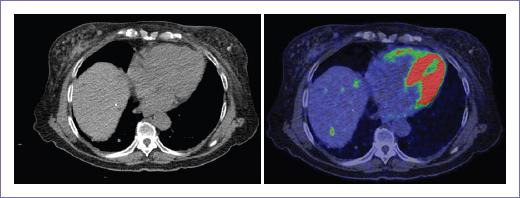

Figura 3 Metástasis hepáticas hipermetabólicas en paciente con antecedente de adenocarcinoma en la unión recto-sigmoides, no visualizadas por tomografía computarizada.

También se realizó el análisis basado en pacientes para ganglios linfáticos locorregionales, ganglios linfáticos a distancia, metástasis pulmonares, hepáticas, en sistema nervioso central (SNC) y otros sitios (entre los que se incluyen ovarios, hueso e implantes en tejido celular subcutáneo). La PET-CT identificó ganglios linfáticos locorregionales en el 66.7% de los casos frente al 33.3% que logró identificar la TC (10 vs. 5), también fue superior para la detección de ganglios linfáticos a distancia (3 vs. 1) y metástasis hepáticas (3 vs. 2); además identificó una lesión ósea que no fue detectada por TC.

Ambos presentaron resultados comparables para las metástasis pulmonares y en ningún paciente se detectaron metástasis en el SNC. En total la PET-CT logró detectar un total de 30 lesiones, en comparación con la TC, que detectó un total de 18 lesiones, ambas incluyendo la lesión primaria.